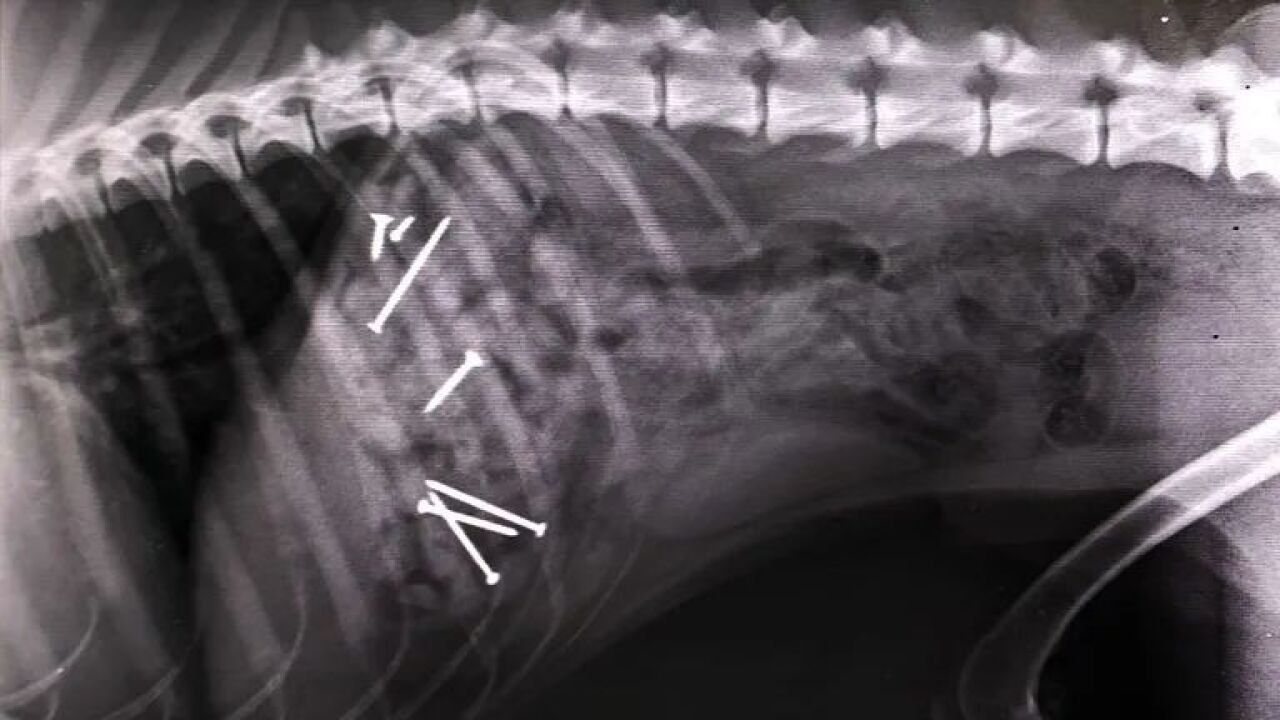

Perro al que intervinieron hace dos años por comer salchichas con clavos en VigoAntena 3 Noticias

En la primera de las ubicaciones se han encontrado salchichas con clavos en su interior. Las esconden entre las hojas y el olor atrae a los perros. Cuando el animal ingiere la comida, es básico llevarlo a un veterinario para que pueda operar al can y evitar, así, la muerte. Pero no es el único cebo que se ha encontrado en los últimos días. En el Arenal la trampa va más allá.